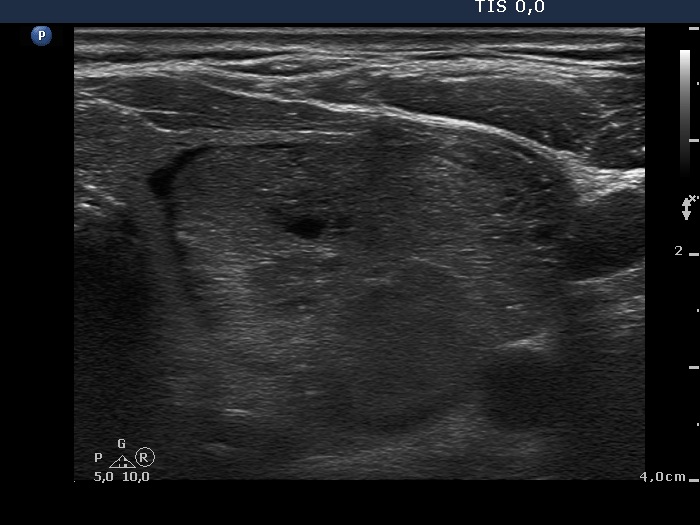

Ultrasonography. The right thyroid was intact. A large nodular area occupied almost the entire left thyroid. It was composed of moderately hypoechogenic, cystic, echonormal and hyperechogenic discrete lesions. The whole lesion was surrounded with an incomplete halo and presented a type 2 vascular pattern.

The sonographic pattern, i.e. a large nodular area composed of discrete lesions with different echogenicity is characteristic of a benign, hyperplastic nodule.